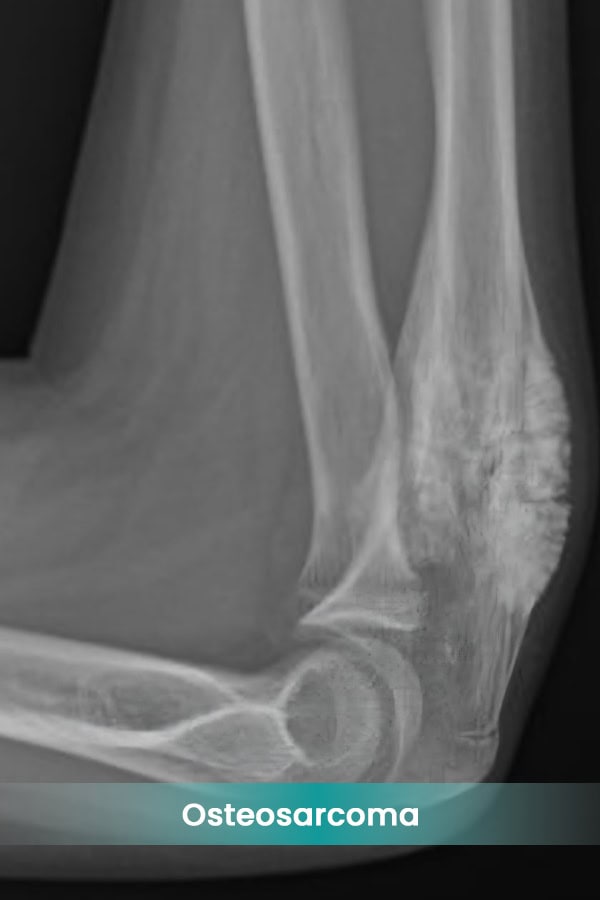

- Osteosarcoma